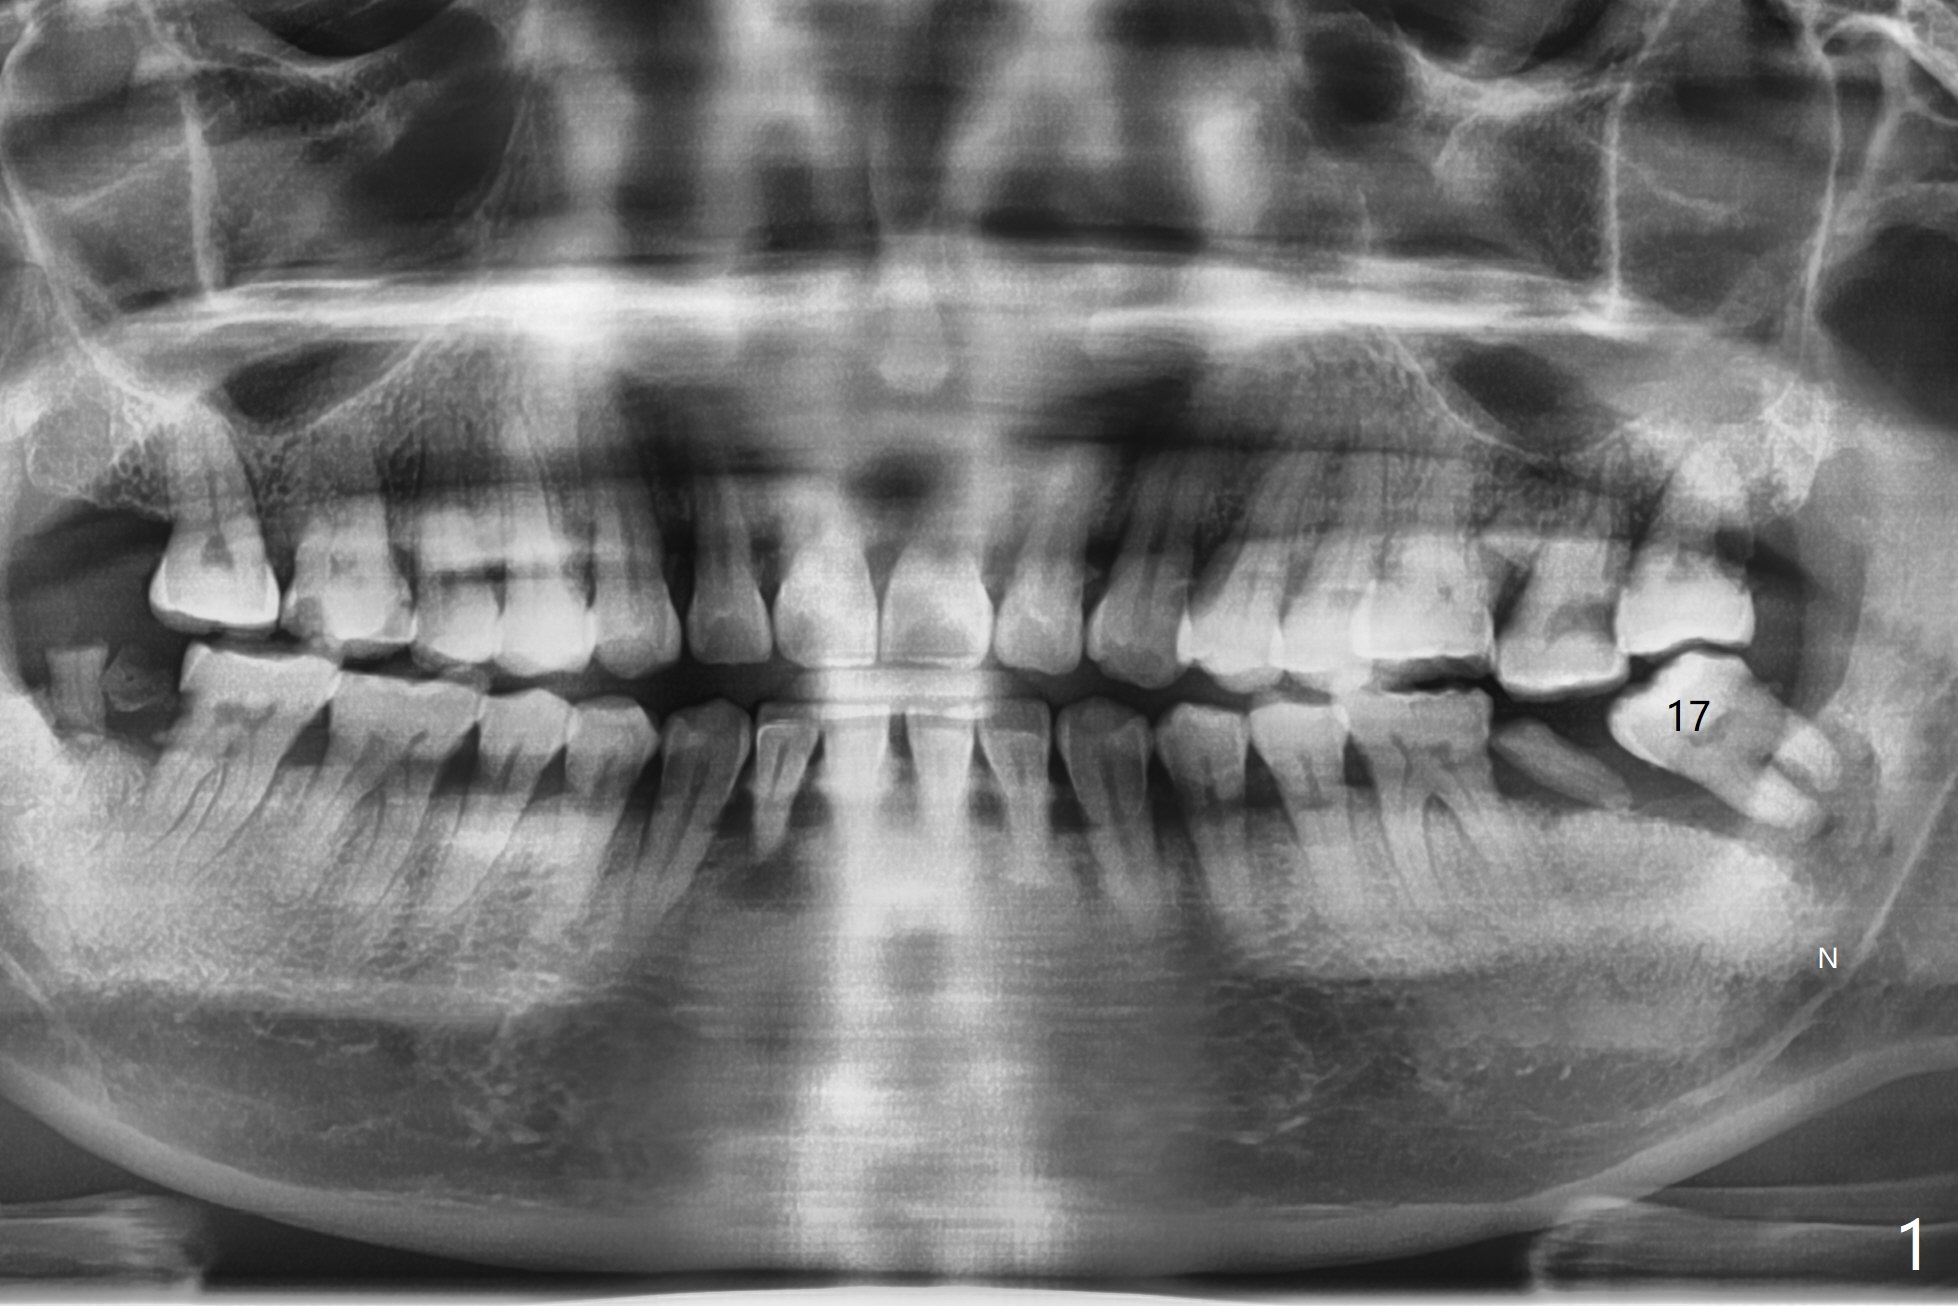

Inferior Alveolar Canal

A 52-year-old man requests extraction of the tooth #17 with severe chronic periodontitis. The socket is large and communicates apparently with the Inferior Alveolar Canal (Fig.1 N). Heavy granulation is removed except the most apical. Two pieces of Collagen Plug are inserted, followed by 4-0 Chromic gut suture. It is expected that ossification occurs in the coronal socket in 3-4 months.